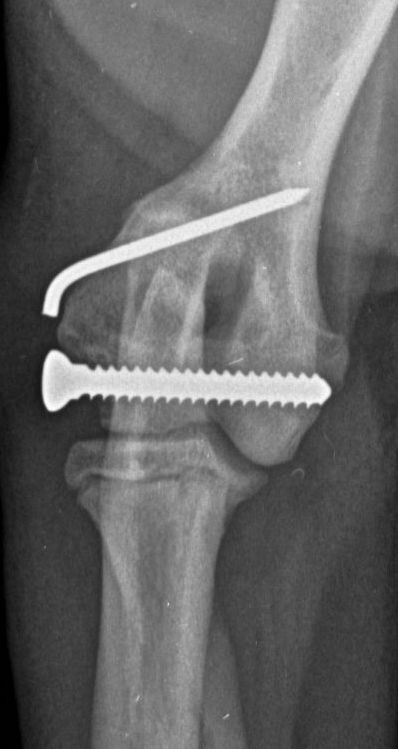

Only 29 dogs (30 fractures) returned for a follow-up examination at 31 to 60 days (median: 42 days), but all these fractures showed complete radiographic union (Figure 4). No minor complications were recorded in any of these patients. Four (13 percent) experienced a major complication: one was noted during the healing phase and three during the follow-up examination. All involved implant migration and all were successfully managed by implant removal or replacement. The short-term outcome was recorded as excellent in 23/30 fractures (77 percent) and good in 7/30 (23 percent).